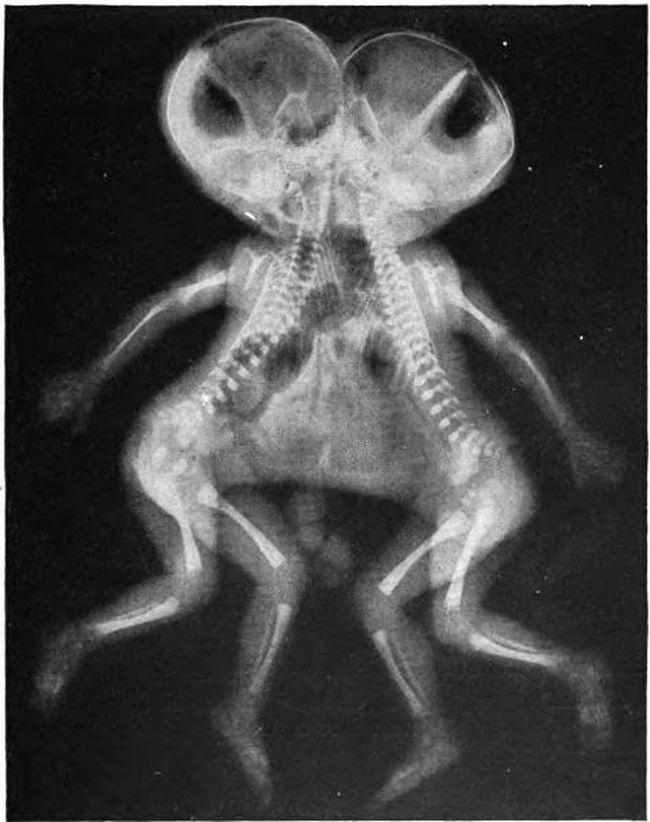

16 – Um raio X de gêmeos siameses